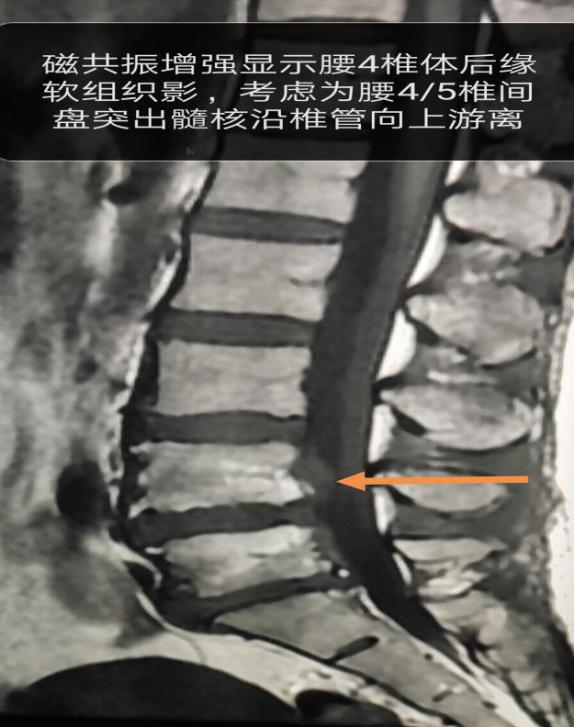

通过查体及症状体征表现、结合影象检查图片和报告,杨四海高度怀疑患者不是单纯性中央型椎间盘突出。回忆起当时的情况他依旧很激动:“我始终觉得这里有个什么东西,但其他人都认为这个是正常的软组织。”杨四海一边指着照片一边说道。在他的坚持下,通过CT重建、磁共振结合增强,最终确诊为“腰4/5椎间盘突出、髓核沿椎管向右后上方脱出”。

手术过程图示